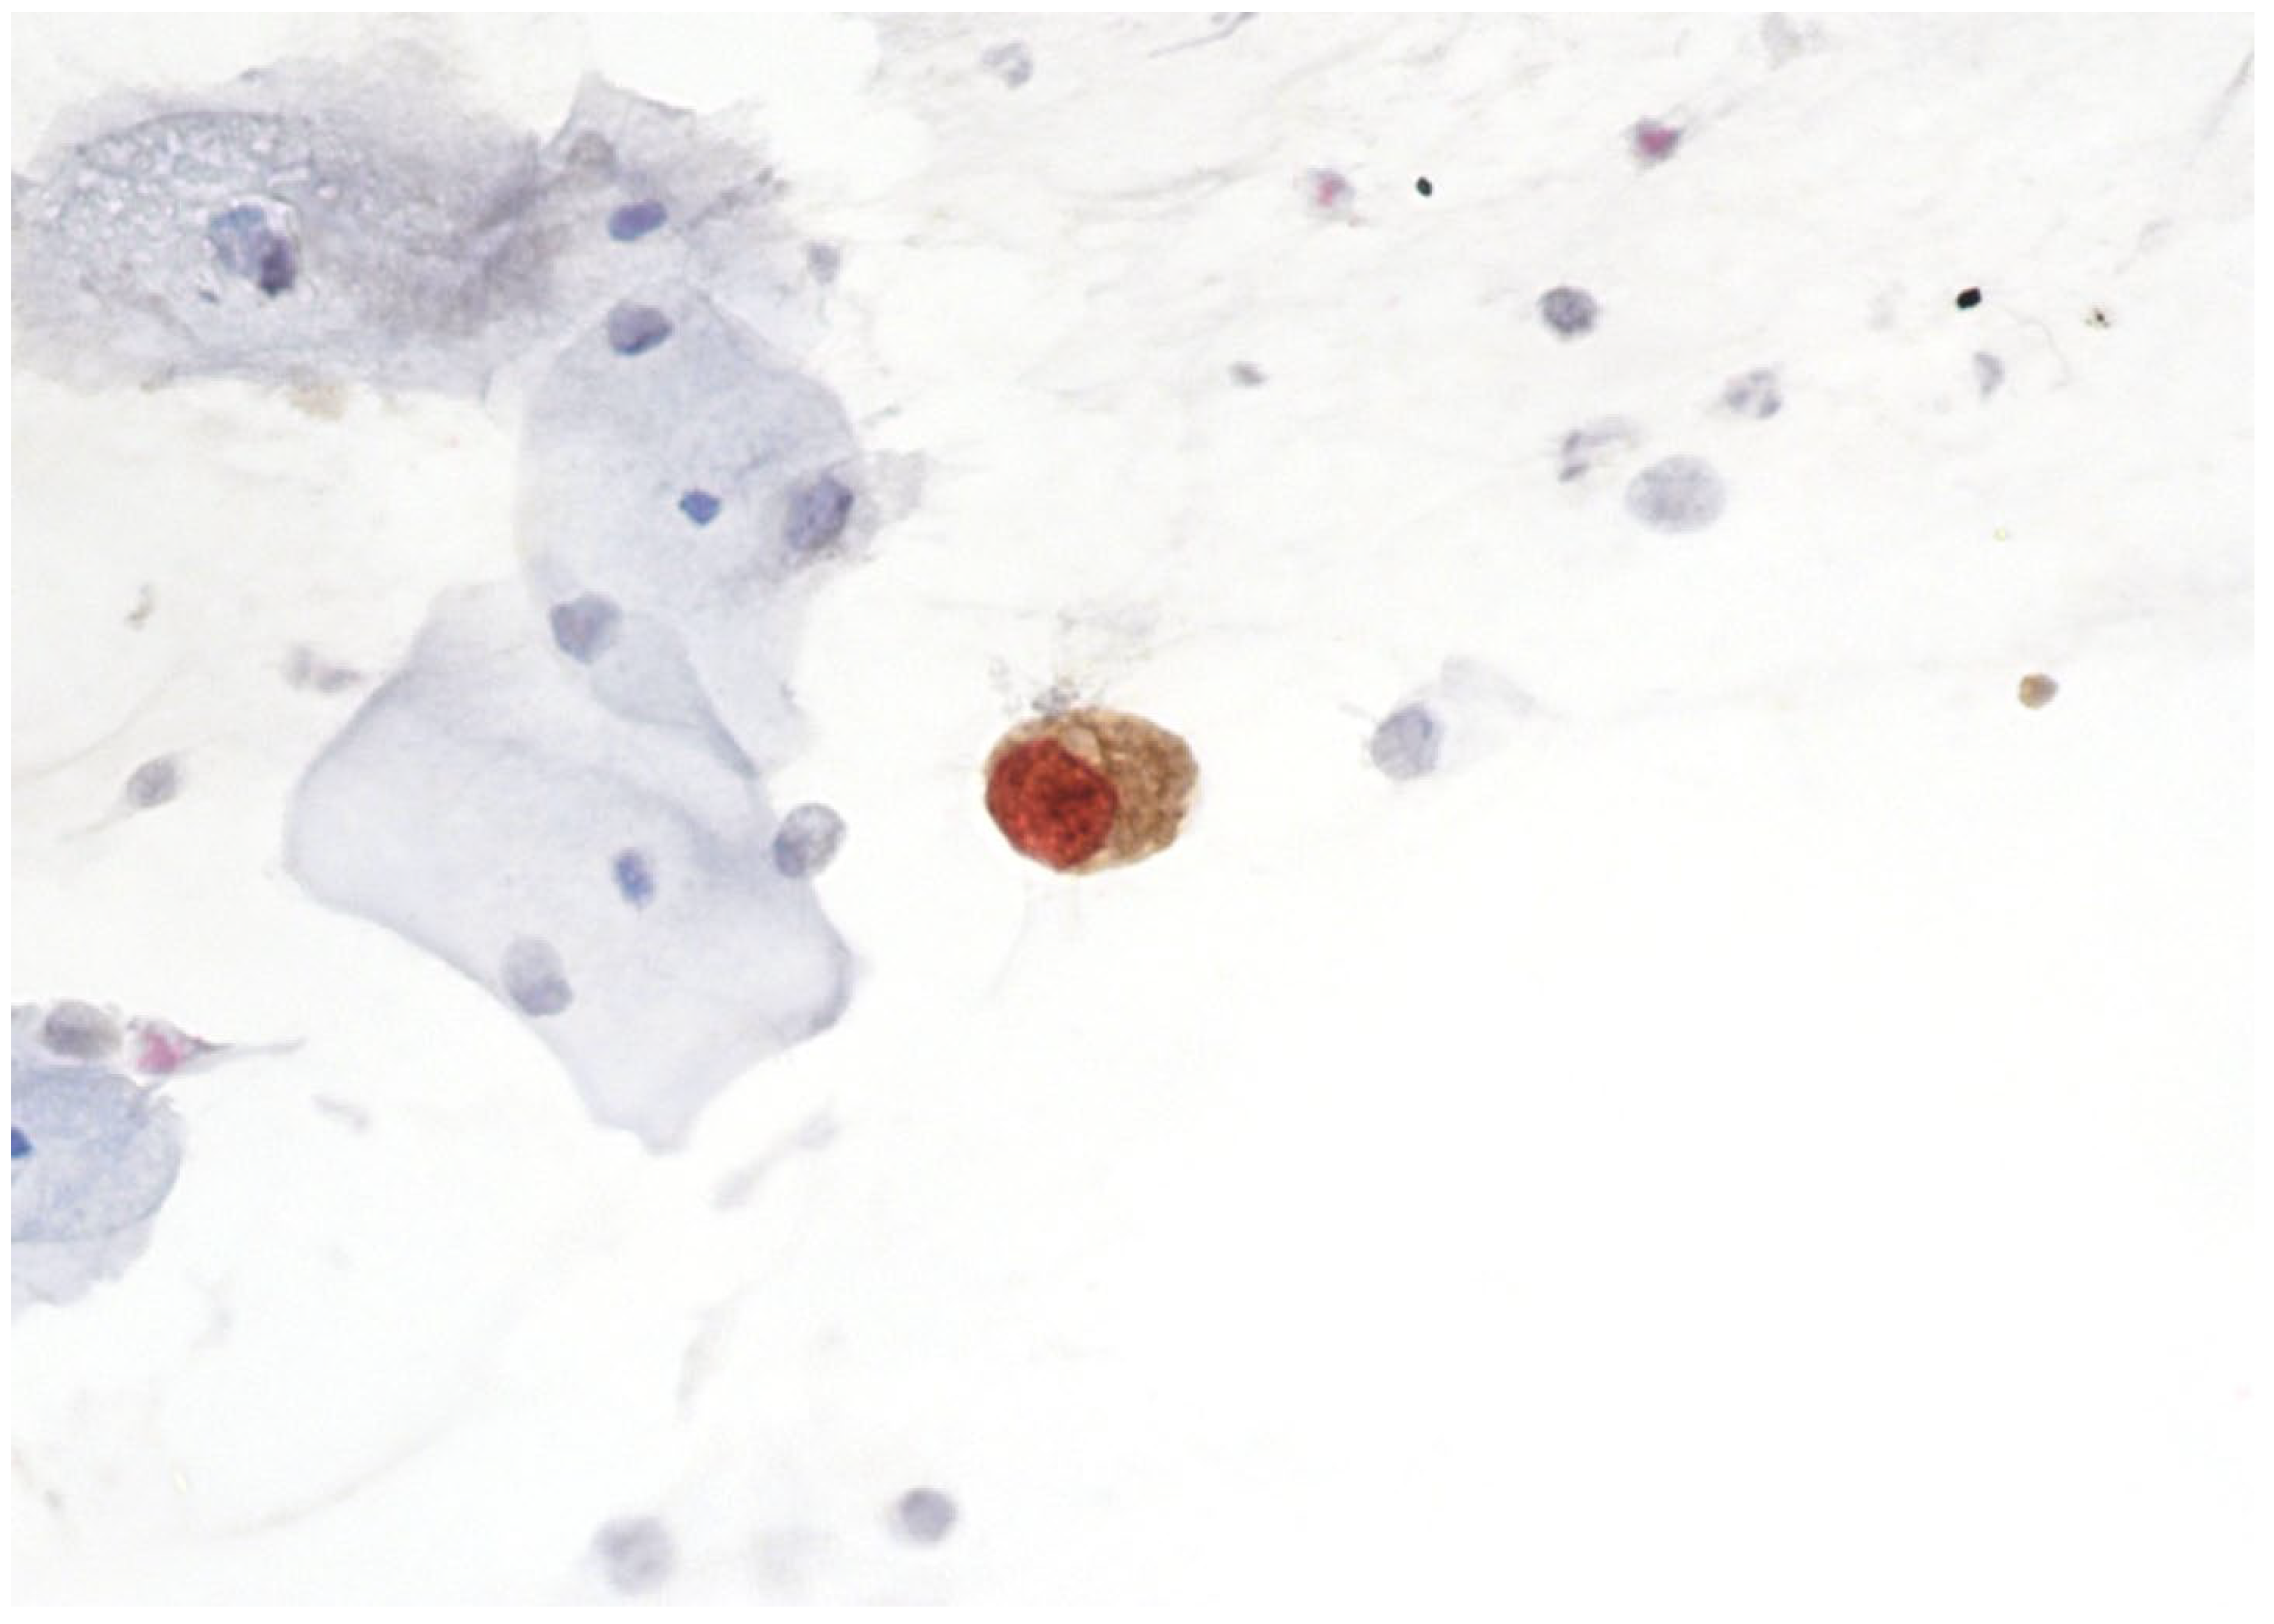

4. Molecular Biology of Cervical Precancerous Lesions and Cervical Cancer

5. The Rationale and Use of p16/Ki67 Dual Staining in Cervical Cancer Screening